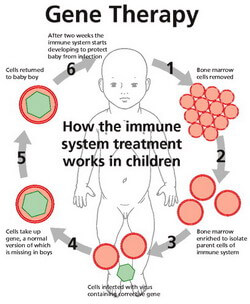

Learn More...What is the treatment for pneumonia in children?

Specific treatment for pneumonia will be determined by your child's primary care provider based on: Treatment may include antibiotics for bacterial and mycoplasma pneumonia. There is no clearly effective treatment for viral pneumonia, which usually resolves on its own.

What is pediatric pneumonia? Pneumonia is an inflammation in one or both of the lungs that is almost always caused by a viral or bacterial infection. The inflammation interferes with the body's ability to deliver oxygen and remove carbon dioxide from the blood.